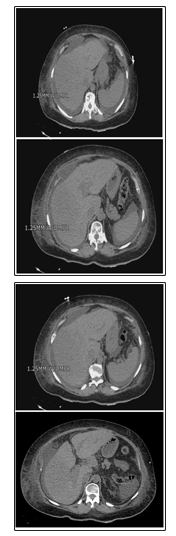

A 61-year-old female with past medical history of multiple sclerosis presented with 2 weeks of generalized weakness with intermittent diarrhea. Her home medications included: baclofen, dalfampridine, glatiramer, glipizide, liraglutide, lisinopril-hydrochlorothiazide, metformin, pregabalin, and venlafaxine. On physical exam, she had bilateral lower extremity edema with right greater than left as well as erythema of right lower extremity. Laboratory data revealed blood urea nitrogen (BUN) 52 mg/dL, creatinine 2.15 mg/dL, total bilirubin 1.2 mg/dL, direct bilirubin 0.4 mg/dL, alkaline phosphatase 232 U/L, ALT 65 U/L, AST 144 U/L, GGTP 605 U/L, and lactate 2.8 mg/dL. Her transaminitis pattern was consistent with a cholestatic pattern with R factor of 1.1. Computed tomography of the abdomen and pelvis (CT) imaging revealed abdominal lymphadenopathy with nodularity of liver with an approximately 3-cm mass in the right hepatic lobe.

Then, the patient underwent a diagnostic paracentesis which showed a serum ascites albumin gradient (SAAG) of 1.9 and a fluid protein of 2.7 g/dL. Following the paracentesis, her mentation worsened, and she progressed to kidney and liver failure. The patient was empirically started on lactulose for suspected hepatic encephalopathy which improved her overall mentation. The patient’s renal function still continued to deteriorate throughout the course of hospital stay, despite treatment with IV fluids and albumin. The patient’s transaminase pattern now showed a mixed pattern of injury of both cholestatic and hepatic with an R factor 4. Treatment with IV fluids for acute renal failure worsened her diffuse edema and anasarca, so the patient underwent a therapeutic paracentesis with removal of 4 liters of peritoneal fluid. Afterwards, her transaminases showed a primary hepatocellular injury pattern with R factor 14. With alpha fetoprotein (AFP) levels of 1700, the diagnosis of HCC was confirmed as a value greater than 500 supports the diagnosis of HCC without further imaging. A transthoracic echocardiogram showed a bilobed mass in the inferior portion of the right atrium: